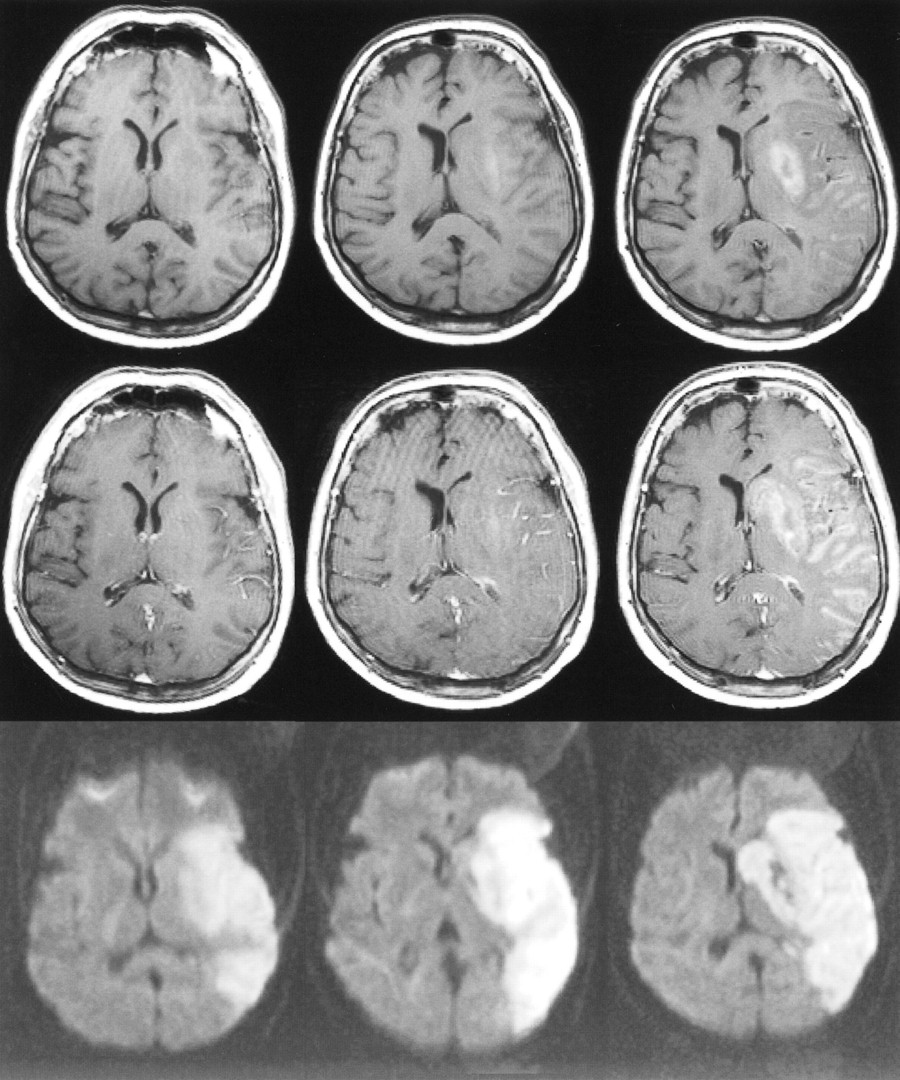

71-year-old man with left hemiparesis. The first MR examination (left column) was performed 15 hours after the onset of symptoms, the second MR examination (middle column) was performed on the second day, and the third MR examination (right column) 1 week after stroke.

Top row, Unenhanced T1-weighted images (600/14/1) show progressing low signal mass effect of the infarcted tissue. Hemorrhagic transformation is detected as areas of increased signal intensity on the second day and at 1 week.

Middle row, Contrast-enhanced T1-weighted images (600/14/1) show intravascular enhancement over the infarct on the first and second days. Moderate cortical and subcortical enhancement are detected on the second day. Intense parenchymal enhancement is detected in the infarct at 1 week.

Bottom row, Diffusion-weighted trace images (4000/103/1, in raw image acquisition) show the extent of infarcted tissue as areas of increased signal intensity in the territory of the right middle cerebral artery. Hemorrhagic transformation is detected as dark areas due to the susceptibility effect of the breakdown products of hemoglobin.